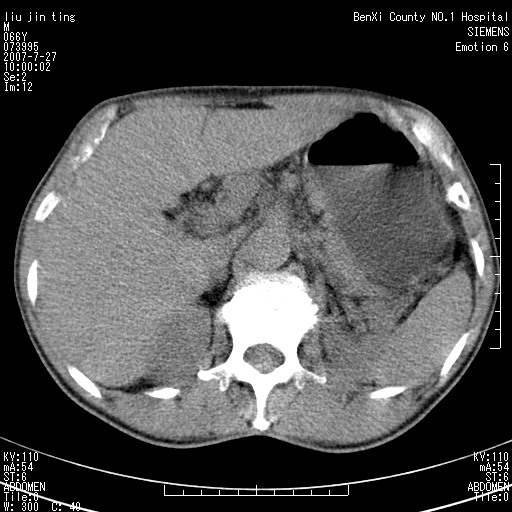

腹痛,背痛,无恶心呕吐,不黄,彩超示胰腺钩癌,ct扫描病灶平扫30-40hu,增强后动脉期40--60hu,静脉期50-68hu,真的是钩突上的么?您要试一试么?

动脉期